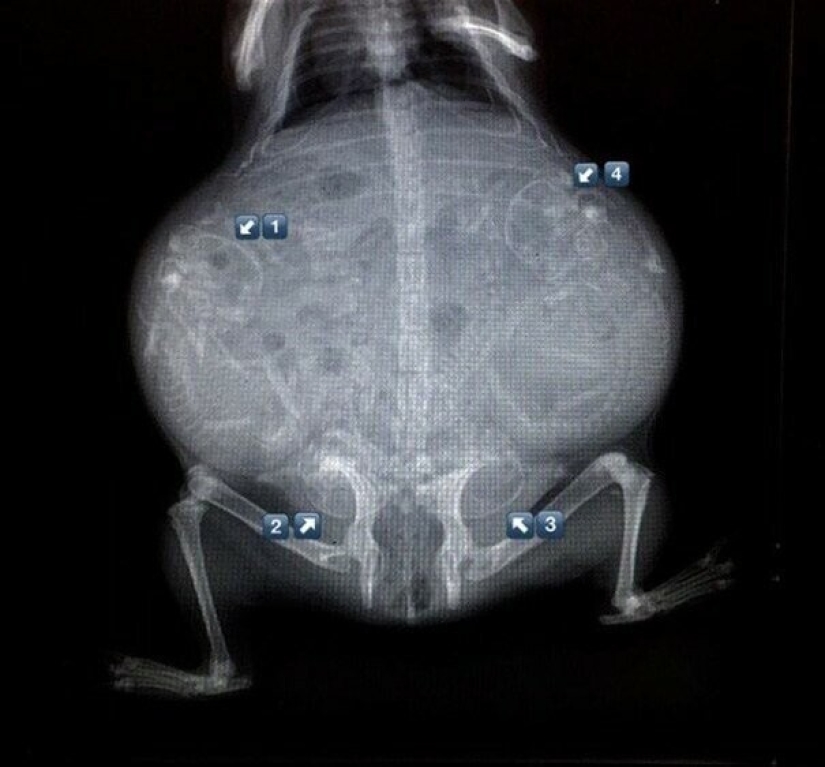

Pregnant turtle